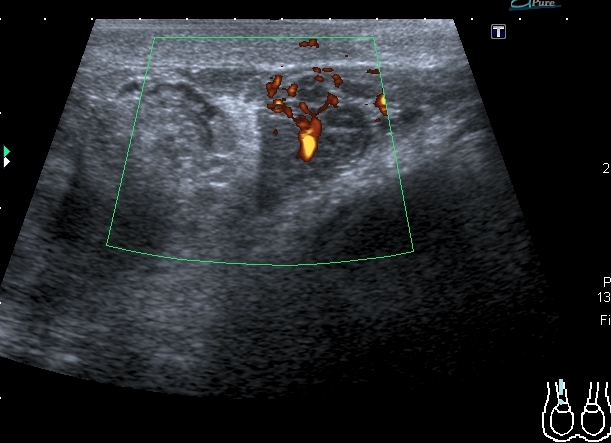

В приёмный покой больницы поступил мальчик 14 лет с жалобами на отёк правой половины мошонки и боли в правом яичке. При УЗИ - правое яичко увеличено отностиельно левого, изменено по структуре, расположено выше левого.

На энергетическом доплере - обогащён кровоток в отёчном придатке и семенном канатике, в яичке кровоток не дифференцируется